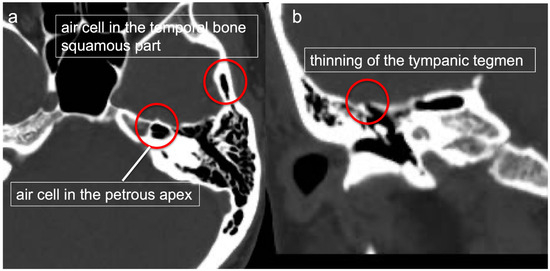

2.1. Preoperative Thin Slice CT (Figure 1)